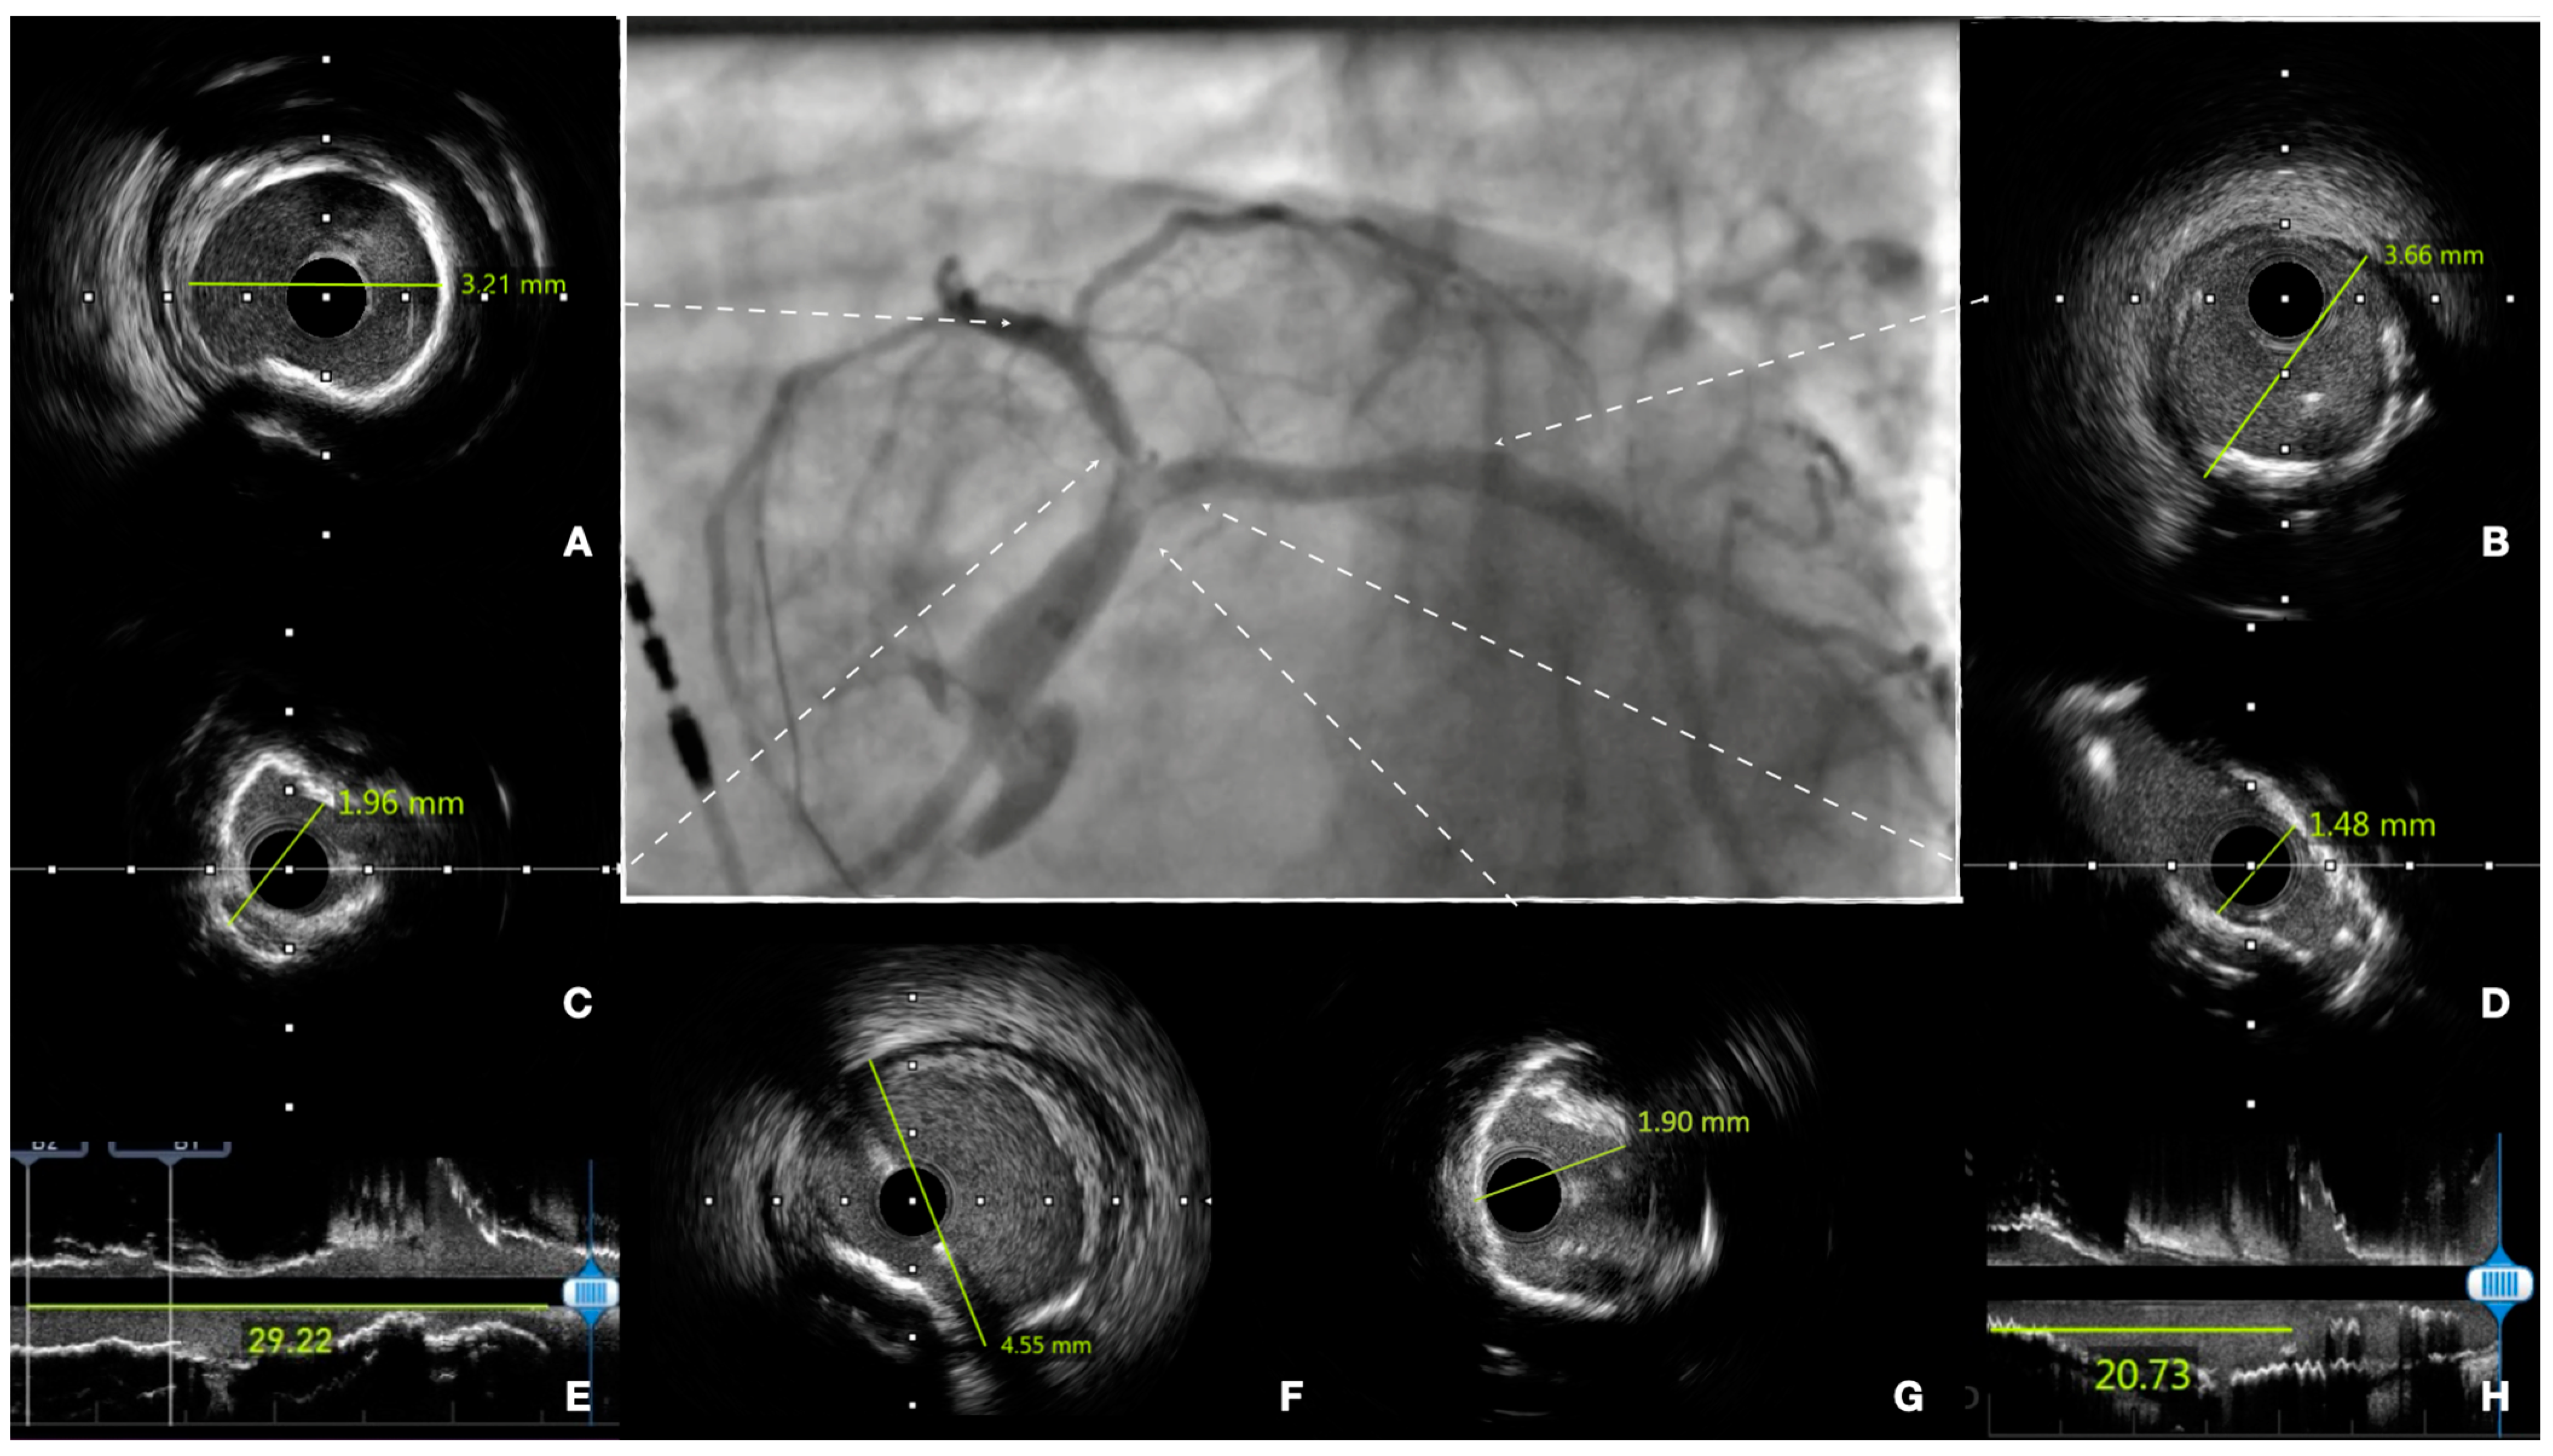

7. Technical Considerations during PCI

8. Intracoronary Imaging Guidance before, during and after PCI